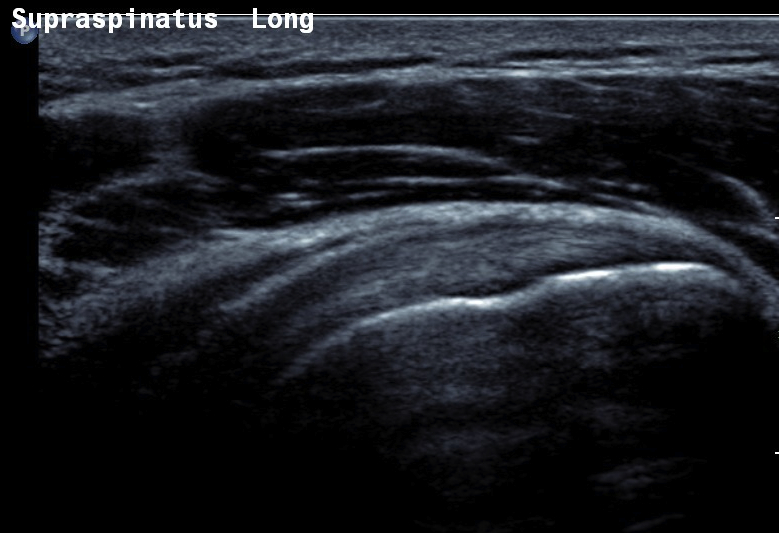

Ultrasound

Normal

- systematic review of US rotator cuff tears

- US more accurate for supraspinatus and biceps than subscapularis

- US more accurate for full thickness tears than partial thickness tears